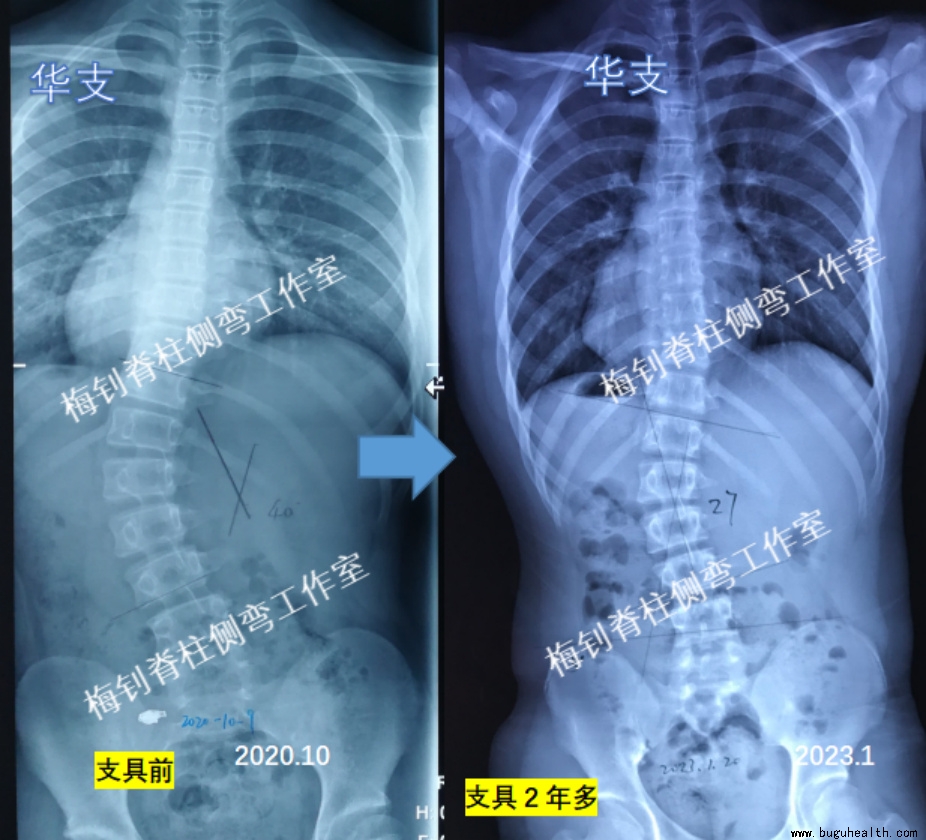

案例3

男孩,2020年10月底来我工作室定制支具及补高鞋垫,当时13周岁,胸腰段侧弯40度,体表旋转达11度。左侧下肢短0.9cm。

2023年1月,孩子穿戴支具2年多,脱支具24小时拍片(拍片时忘记穿鞋垫),主弯曲由40度降低为27度。期间,孩子身高增长8.5cm,体重增加10kg,更换支具2次。此外,体表的剃刀背自穿戴支具1年后就完全恢复正常。